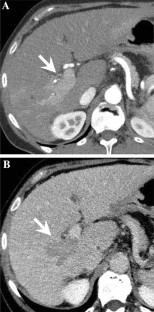

Fig. 3